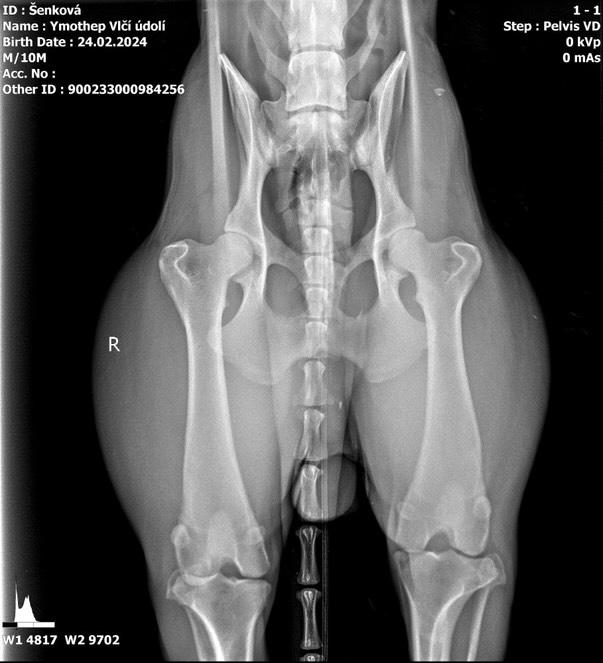

DOB: 02/24/24